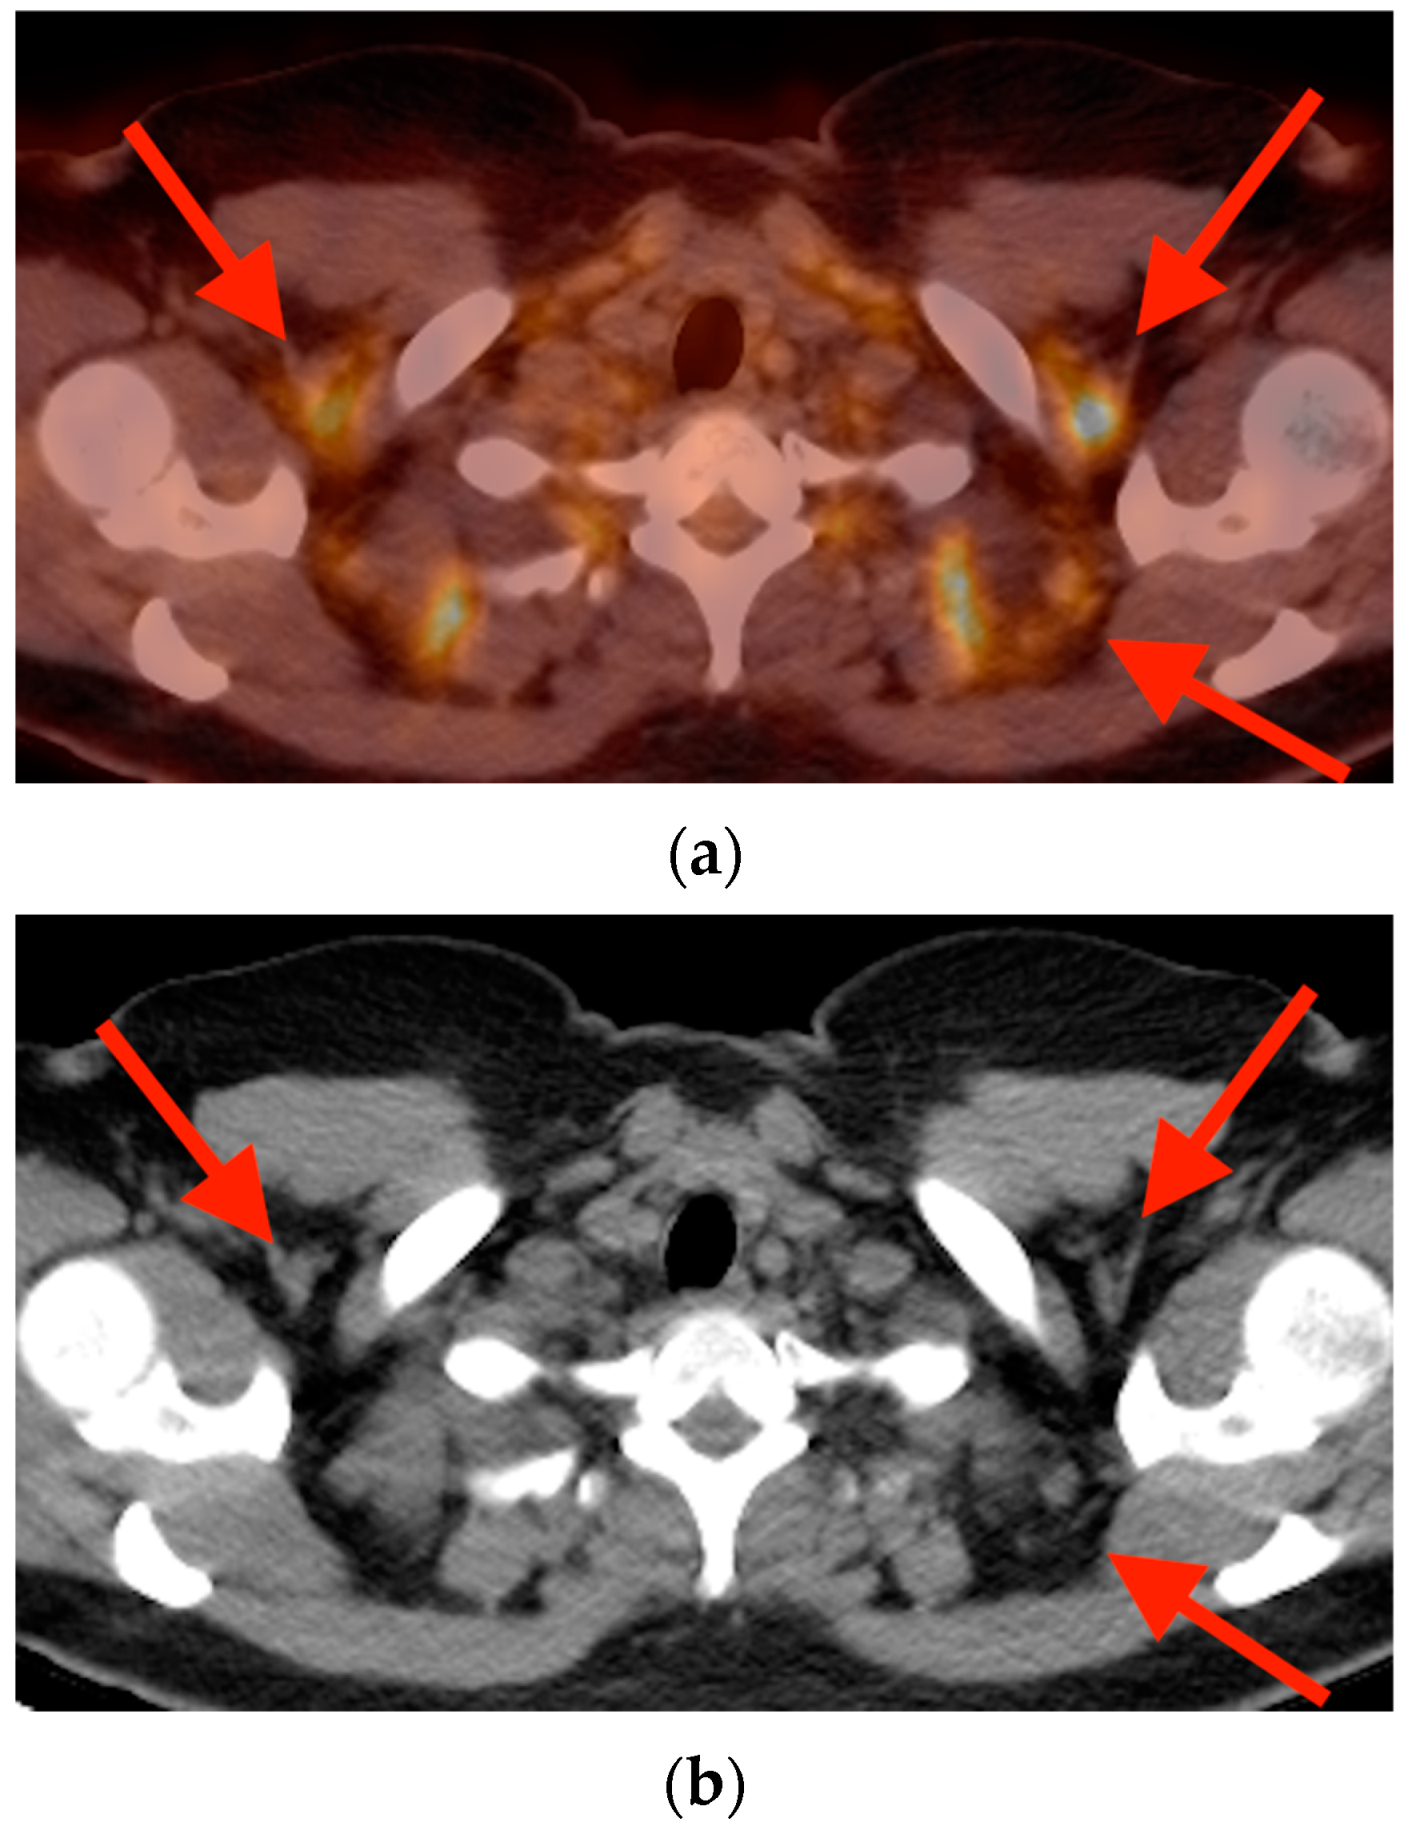

5.2. Brown Fat Activation

5.3. Hibernoma